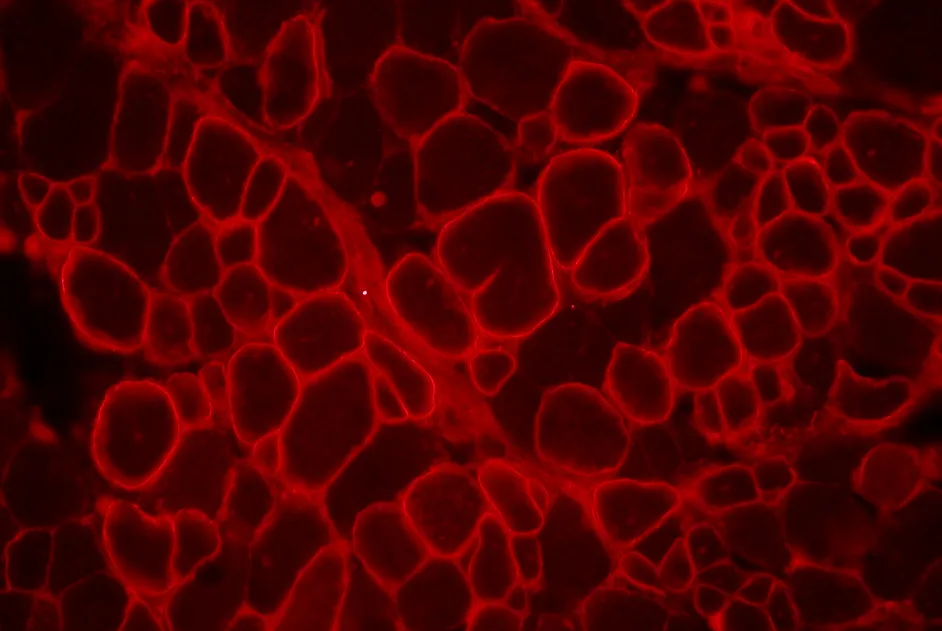

Mise au point du premier modèle de souris présentant une duplication d’exon et récapitulant de nombreuses caractéristiques cliniques de la myopathie de Duchenne